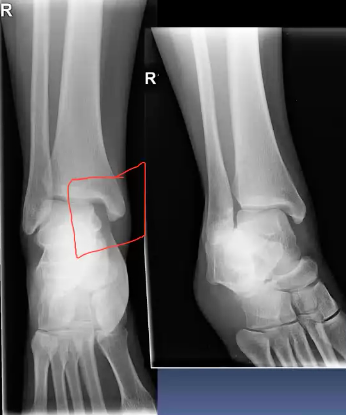

A 30 year old woman presented to the ED with right ankle pain after a fall. She was struggling to walk. Her ankle was swollen and tender on examination. Movement was limited due to pain.

AP and lateral fibula:

What is a maisonneuve fracture?

A combination of a fracture of the proximal fibula together with an unstable ankle injury (widening of the ankle mortise on x-ray)